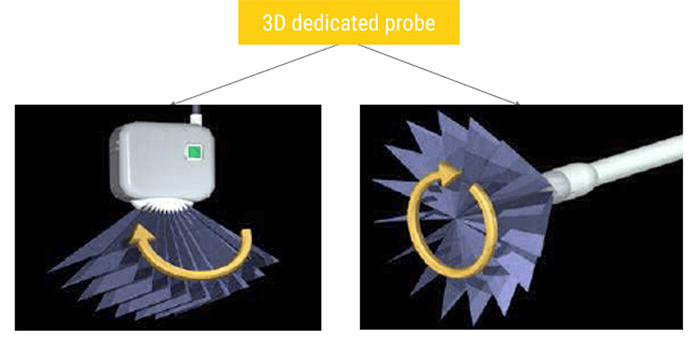

3D Ultrasound

One of the most commonly used imaging modes in gynecology is the 3D mode, which is a series of data that contains a large number of 2D planes (B-mode images).

In general, 3D ultrasound imaging can be conducted with three main stages: acquisition, reconstruction, and visualization. The acquisition refers to collecting the B-scans with relative position using conventional 2D probes or directly obtaining 3D images using dedicated 3D probes. The reconstruction aims to insert the collected 2D images into a predefined regular volume grid. Whereas the visualization is to render the built voxel array in a certain manner like any-plane slicing, surface rendering, or volume rendering.

3D images are acquired using 2D probes or dedicated 3D probes. In a mechanical 3D probe, a regular linear array transducer is motored to tilt, translate, or rotate to emit and receive the ultrasound waves. Two types of mechanical scanning are illustrated, which are tilting scanning, and rotational scanning.